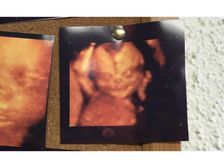

వావ్..! ఈ ఆల్ట్రాసౌండ్ ఇమేజెస్ చూస్తే ఇంప్రెస్ అవ్వాల్సిందే..!!